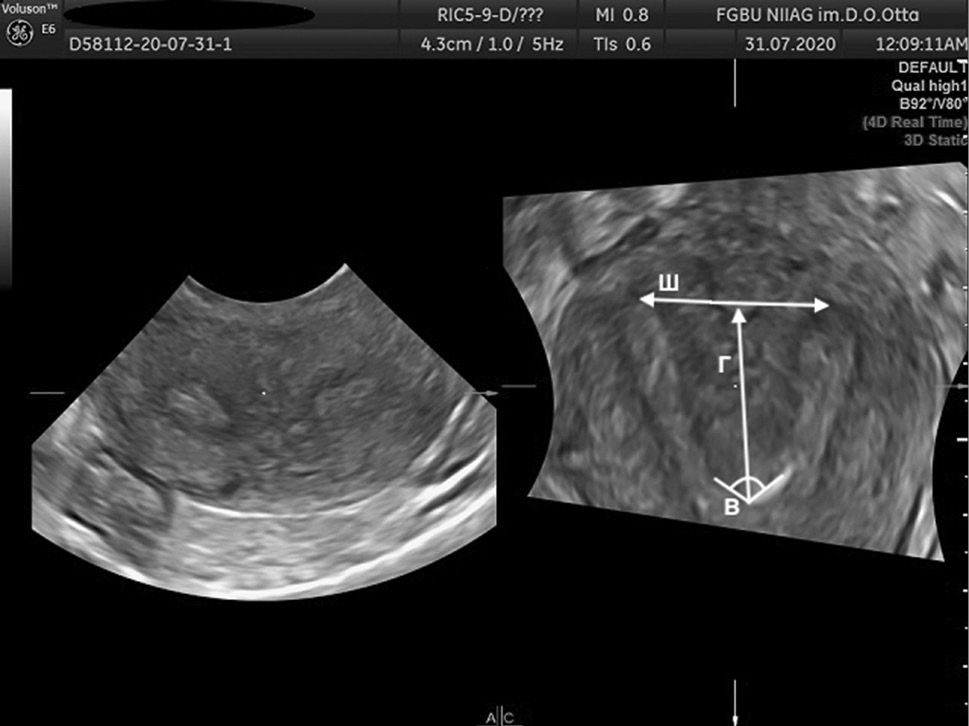

The AFS proposed to assess parameters, such as Г, cavity indentation; Ш, uterine cavity width; and B, angle of cavity indentation (Figs. 1–4).

Fig. 3. 3D ultrasound reconstruction of the uterine cavity: bicornuate uterus, where Ш, uterine cavity width; Г, cavity indentation; B, angle of cavity indentation

Рис. 3. Ультразвуковая 3D-реконструкция полости матки — двурогая матка: Ш — ширина полости матки; Г — глубина вдавления полости матки; угол В — угол вдавления полости

Uterine septum is diagnosed using the following indicators: Г ≥15 mm, angle B <90º, while uterus arcuate is diagnosed using the following indicators: D ≥10 mm, but <15 mm and angle B >90° [11].